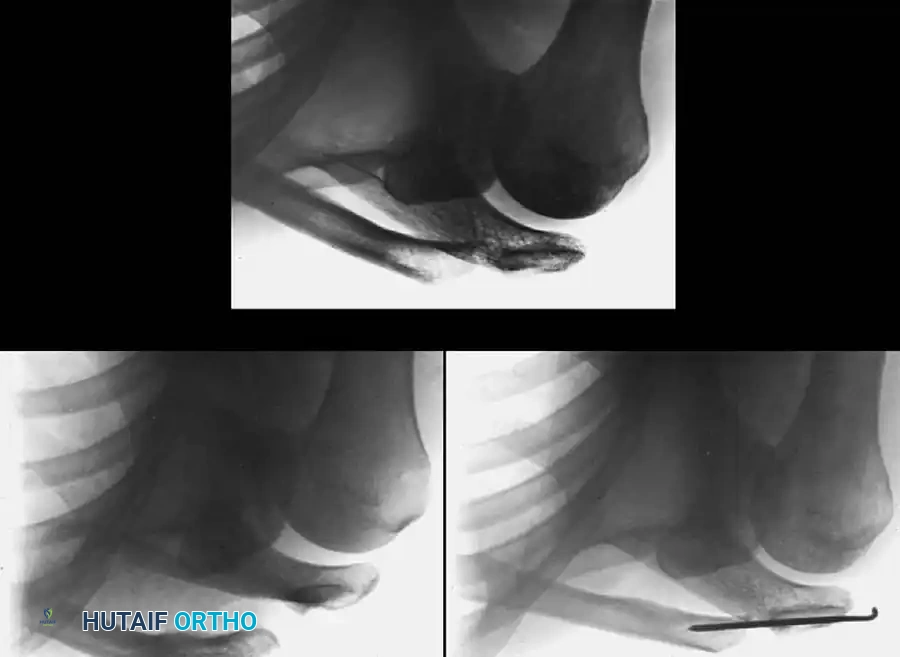

Fig. 57-19 Stewart technique for acute dislocation of acromioclavicular joint. A, Soon after injury. B, Six weeks after surgery. C, Three months after surgery.

5. Postoperative Care: The pins are typically removed at 6 weeks (as seen in Fig. 57-19 B) to prevent hardware breakage, allowing for fibrous healing of the joint (Fig. 57-19 C).